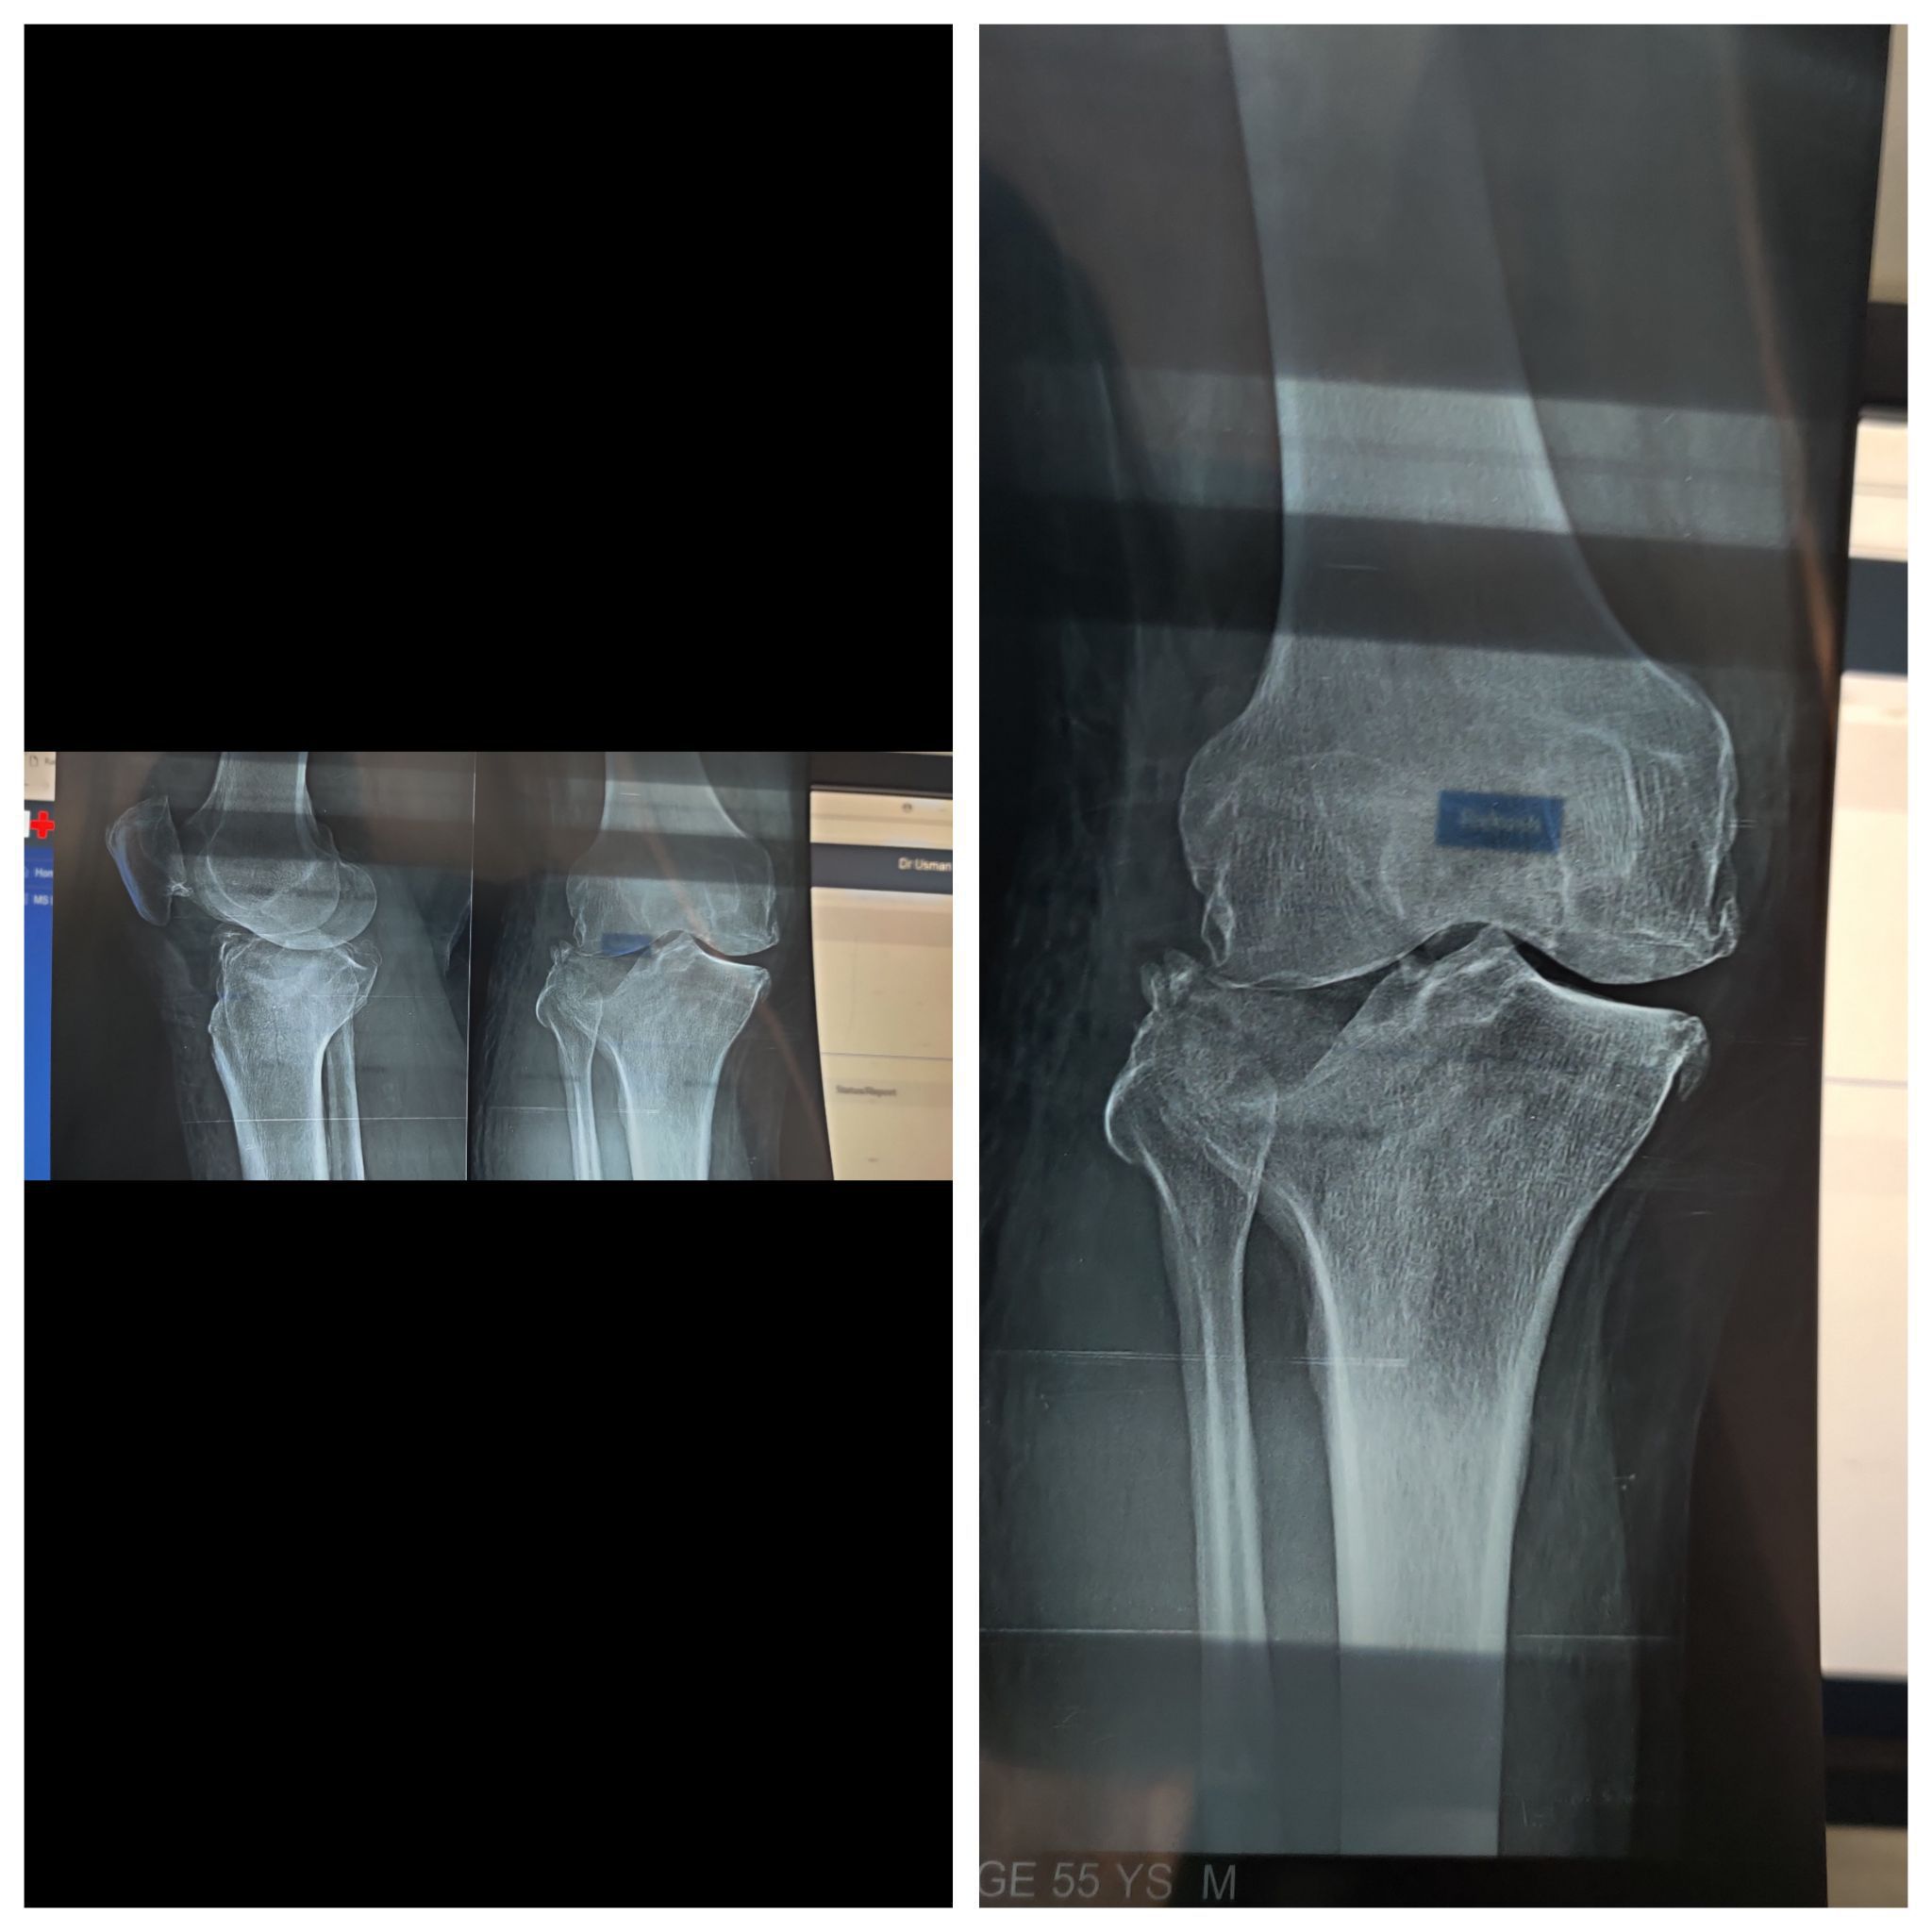

Tibia Fracture

Trauma

Xray

Orthopaedics